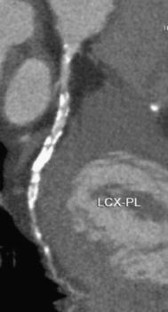

The challenge of coronary calcium on coronary computed tomographic angiography (CCTA) scans: effect on interpretation and possible solutions

Fig. 3

Fig. 4